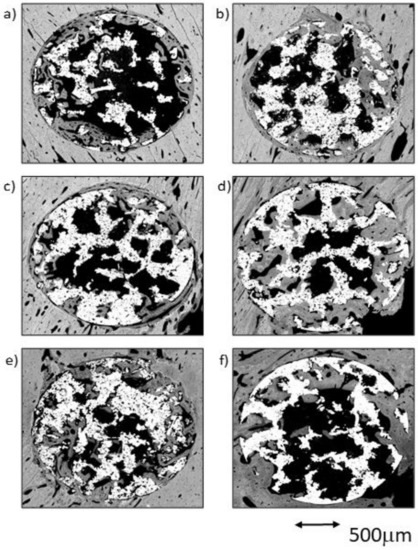

2.3. Quantitative Histomorphometric Evaluation

2.3.1. Postoperative Period Groups after 4 Weeks of Implantation

2.3.2. Postoperative Period Groups 12 Weeks after Implantation

2.4. Qualitative Evaluation in Cross-Section View

2.4.1. Sample Groups 4 Weeks after Implantation

CG Group at 4 Weeks

TCG Group at 4 Weeks

PAG Group at 4 Weeks

2.4.2. Sample Groups 12 Weeks after Implantation

CG Group at 12 Weeks

TCG Group at 12 Weeks

PAG Group at 12 Weeks